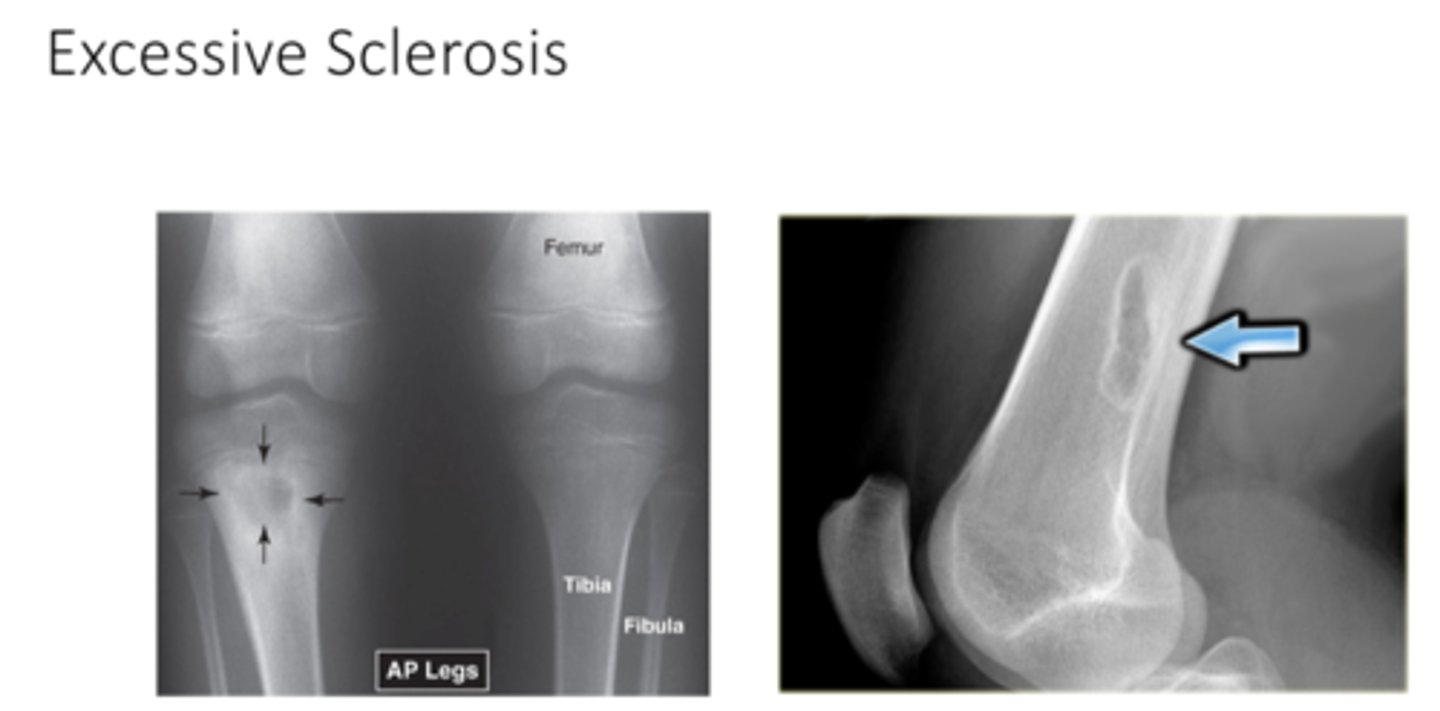

what does Excessive Sclerosis look like